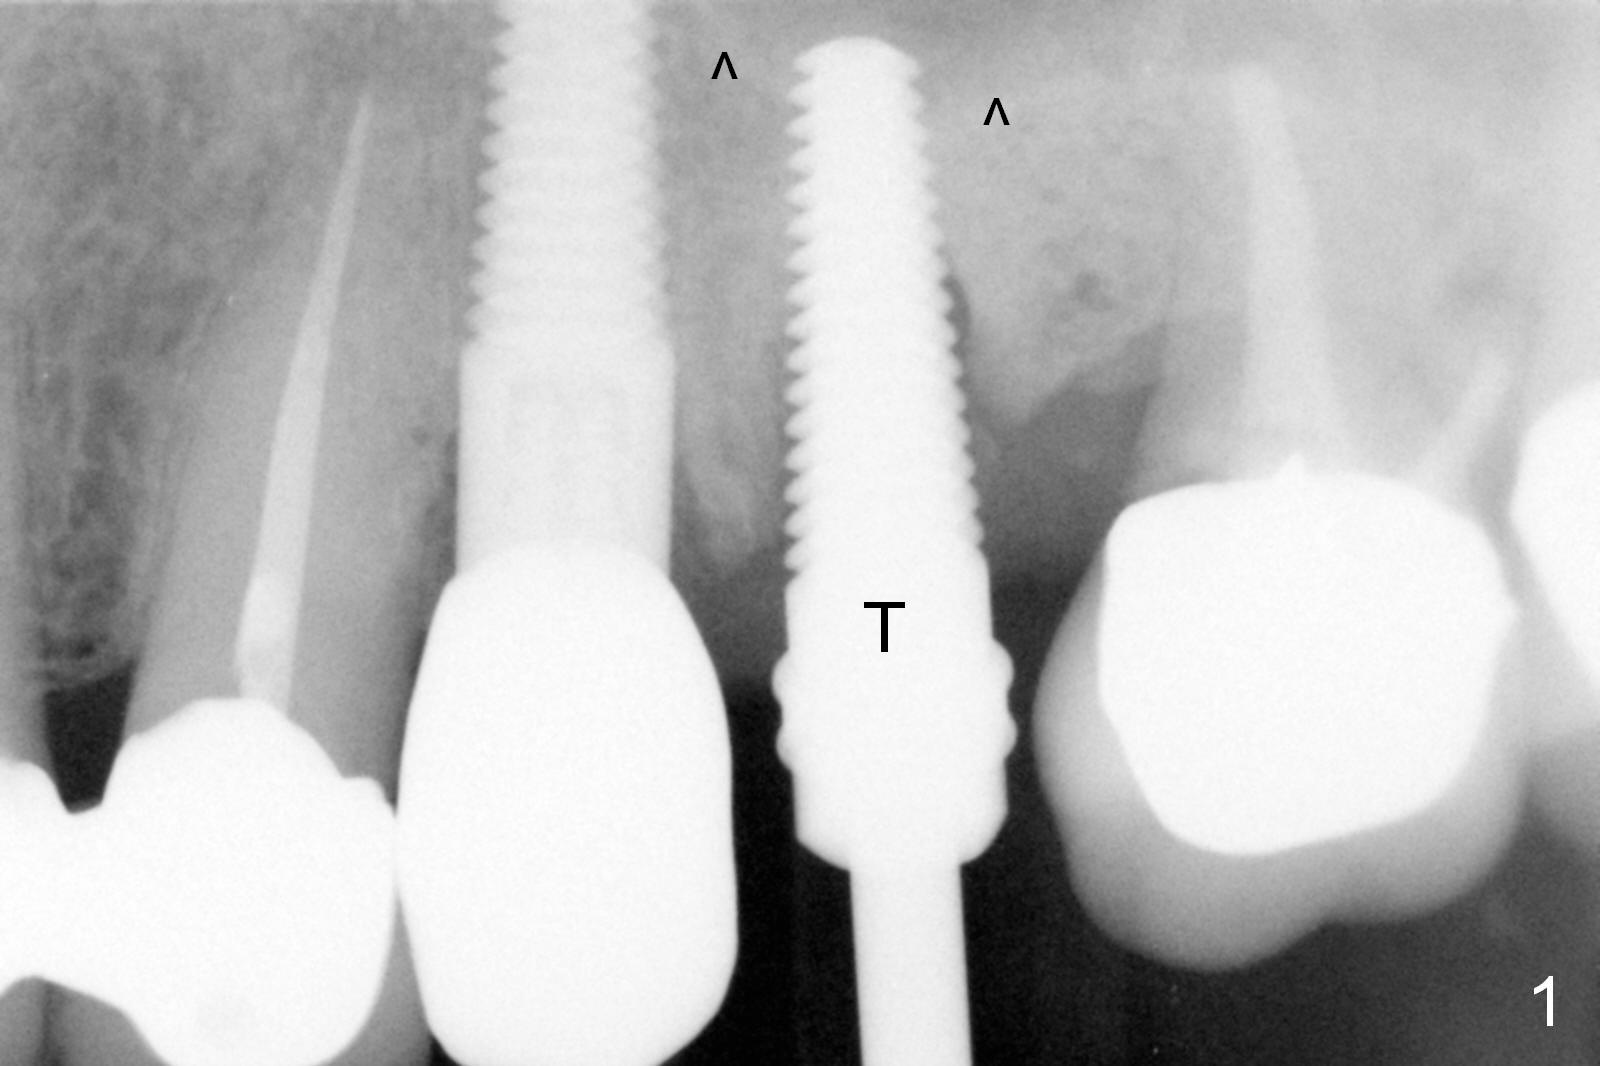

Extraction of the affected 2nd premolar is easy; the apical bone is so hard that drill and reamers have to be used for osteotomy, followed by insertion of a 4.5 mm tap with stability (Fig.1 T). The sinus floor (^) is lifted. There is no sign of sinus membrane perforation before placement of a 4.5x14 mm implant (Fig.2 I); sinus lift is performed (*: autogenous bone mixed with Mineralized Cancellous Human Allograft, Impladent); an immediate abutment (3.5x3 mm) is placed (A). With gauze placed in the buccal gap (Fig.3 G), the margin of the implant (I) is prepared for an immediate provisional fabrication. Mixture of autogenous bone (from reamers), allograft and Osteogen is placed in the remaining socket (Fig.4,5 *). When the relined (1st modification), trimmed and polished provisional is reseated (Fig.6 P), the bone graft (*) is not completely covered. New acrylic (2nd modification) is added to the margin of the provisional (Fig.7 *) for containment of the graft. There is almost no buccal plate; Osteotape (collagen membrane with Osteogen) is placed against the buccal wall of the socket prior to bone grafting. The remaining small pieces of the Osteotape (Fig.7 <) are laid over the bone graft before reseating the final provisional. With "complete socket seal", perio dressing is unnecessary.